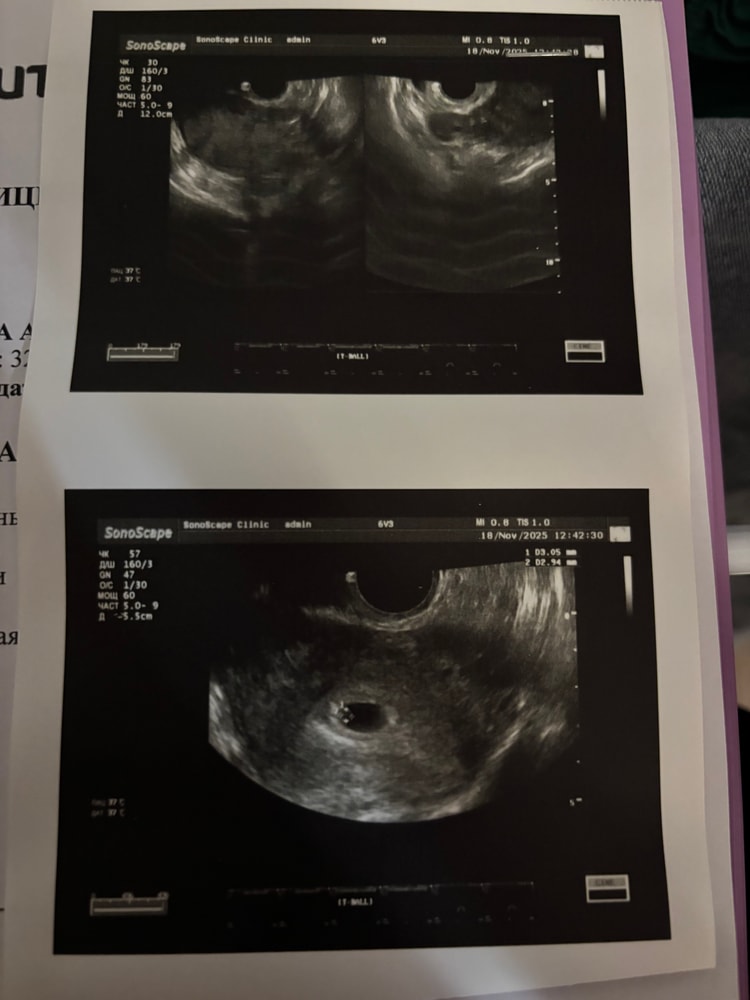

Да всё в порядке, не волнуйтесь, если овуляция была поздней, то срок чуть менее 6 неделек, а на таком строке практически и не возможно разглядеть эмбрион и замерять КТР.

У меня первое УЗИ, при подтвержденной овуляции, было на строке 5 недель +3, и тогда тоже ещё не видели эмбринчика, сказали, что хорошо, что плодное яйцо в матке, и есть ЖМ, для такого строка это главные маркеры, что всё хорошо. А вот через неделю уже был и эмбрион, и сердцебиение.

Поэтому у вас всё хорошо, всё соответствует строку, Нада ещё подождать, и эмбриннчик покажется)

Ох уж я люблю эти заключения) заболевание - беременность) у меня когда спросили тоже какие жалобы я первым делом сказала «отсутствие месячных») по теме - возможно рано пошли, если действительно не знаете дату овуляции. А когда тесты заполосатились? Читала что если есть желточный мешочек то эмбрион скоро тоже визуализируется. В моем случае все было в 6 недель и два дня, но я четко знала дату овуляции, и в моих планах был хотя бы пя и желточный мешочек.

При поздней овуляции, конечно, рано. Да и ПЯ еще маловат.

У меня овуляция была на 25 д.ц., отслеженная. Нашли эмбриончик с сб в 6+3 (по месячным 8+3 было)

Блин. Вот вспоминаю каждый свой «ранний» поход на узи и нервотрепку после него и думаю, нафига я так рано на узи перлась? Понимаю, что у Вас все по протоколу… не переживайте, срок еще маленький, плодное яйцо всего 9 мм. Через недельки полторы сходите и все увидите)